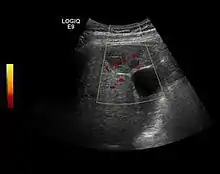

The ultrasound appearance is a well defined lesion, with very thin, almost unapparent walls, without circulatory signal at Doppler or CEUS investigation. The content is transonic suggesting fluid composition. The presence of membranes, abundant sediment or cysts inside is suggestive for parasitic, hydatid nature. Posterior from the lesion the acoustic enhancement phenomenon is seen, which strengthens the suspicion of fluid mass. They typically displace normal liver vessels but no vascular or biliary invasion occurs.